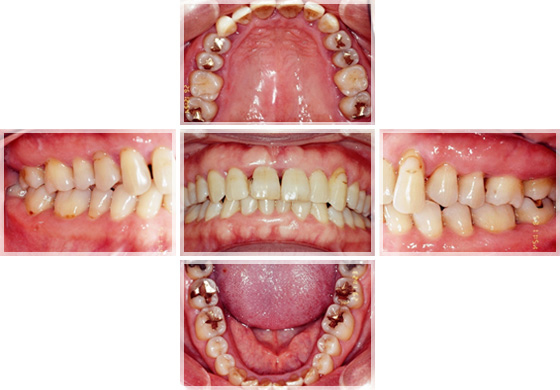

3. 口腔内撮影

治療の進行に応じて、見た目の変化を追いながら、患者さんにも視覚的に理解していただくために、お口の中の写真を撮影します。